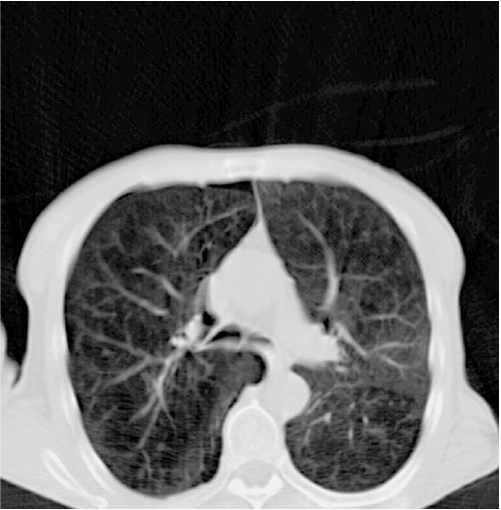

所有的肺活检都有相同的风险吗、 do lung biopsies all have the same risk?

![]() |

| 肺结节,拟穿刺活检 | 从哪入路? |

| 选择背侧入路 | 昏迷,癫痫发作 |